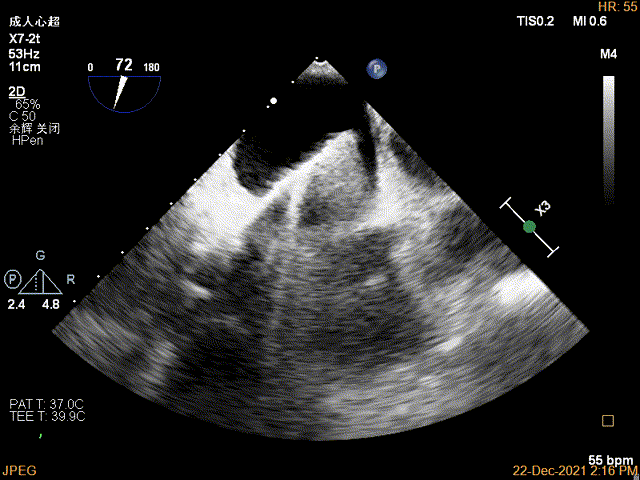

3D MV View:P2区脱垂

Qlab软件勾画估测瓣口面积约:7.19cm²

TEE Bicom view:二尖瓣后叶P2区大范围脱垂,部分累及1区及3区